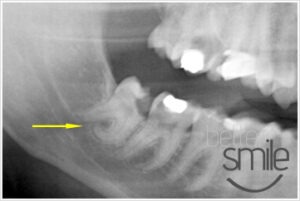

- Dolna ósemka, dodatkowym utrudnieniem jest bardzo mocne zakrzywienie korzeni.